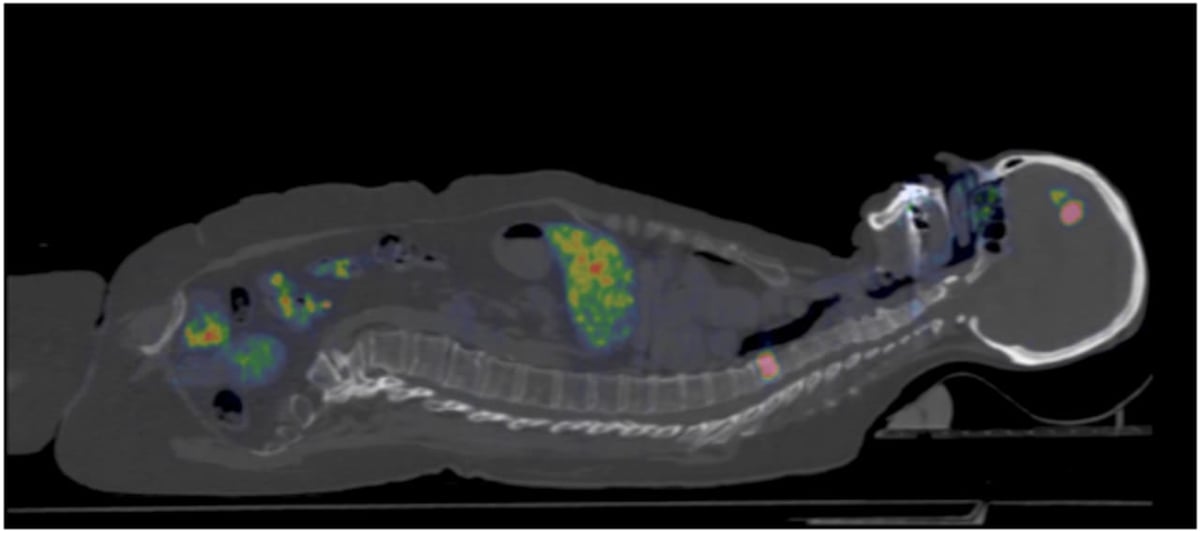

Den nya pet-metoden innebär att man använder ett litet protein/spårämne, en så kallad affibody, som kopplas till radioaktivt Gallium på pet-centrum vid Akademiska sjukhuset. Proteinet fungerar som målsökare och fäster vid HER2-proteinet. Proteinet sprutas in i ett blodkärl och transporteras vidare till resten av kroppen. När det fastnar i vävnader med mycket av HER2-protein kan pet-kameran läsa av radioaktiva signaler.

Effektivare diagnostik av bröstcancer utan biopsier är målet för en nordisk studie ledd från Akademiska. Forskarna använder pet-kamera och ett nytt spårämne.